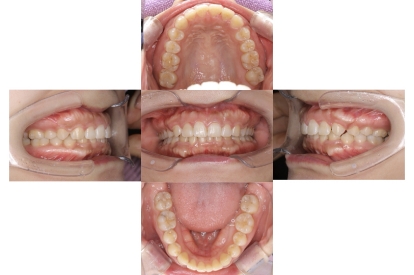

BEFORE

AFTER

上下顎前突、叢生

抜歯

ブラケット矯正

上下顎前突、叢生(上下出っ歯、上下の前歯のガタガタ)のケースです。

装置はラビアル(上下表側)で、上下顎の小臼歯を4本抜歯を行っています。抜歯したスペースを使って、上下の前歯の後方移動と叢生(ガタガタ)の改善を行っています。

主訴 前歯のガタガタと口元がでているのが気になる。

年齢・性別 30歳 女性

お住まいの地域 東京都大田区

治療方針 抜歯スペースを利用して上前歯の叢生(ガタガタ)と口元突出の改善

抜歯部位 上下顎左右第一小臼歯

使用装置 ラビアル(上下表側)、顎間ゴム

治療期間 1年11か月

治療回数 13回

リテーナー クリアリテーナー